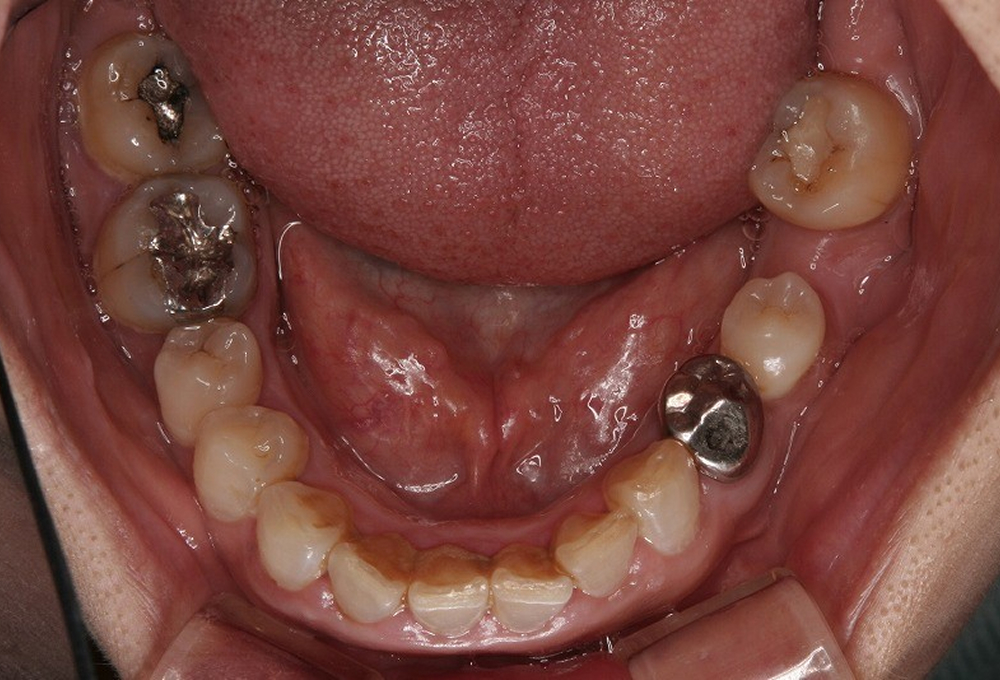

③術前下顎